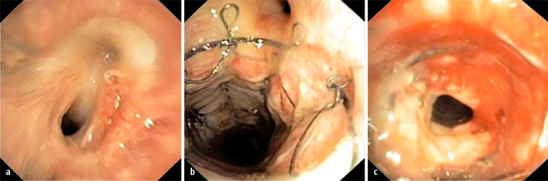

Die im ersten Jahr häufige akute Abstoßung verläuft selten lebensbedrohlich. Unspezifische Symptome wie Husten, subfebrile Temperaturen, Luftnot, Hypoxämie, Pleuraerguss, interstitielle Infiltrate oder ein Abfall der Lungenfunktion können auftreten. Histologisch besteht eine lymphozytäre Infiltration der terminalen Bronchioli und begleitender Gefäße (Abb. 3). Eine internationale Klassifikation ist etabliert [32]. Die akute Abstoßung ist nach einem Steroidpuls (Methylprednisolon 15 mg/kgKG/Tag für 3 Tage) meist vollständig reversibel.

Trigger des BOS, das als progrediente obstruktive Ventilationsstörung imponiert, scheinen wiederholte akute Abstoßungen, virale Infekte, mangelhafte Therapieadhärenz, Aspiration sowie ein gastroösophagealer Reflux zu sein. Jeder 2. Empfänger ist 5 Jahre nach Transplantation von einem BOS betroffen. Histologisch imponiert eine Obliteration der Bronchiolen (Abb. 4).

Die Prävalenz relevanter Atemwegskomplikationen liegt bei etwa 20%. Unterschieden werden Nekrosen und Obstruktionen neben den seltenen Torsionen. Risikofaktoren scheinen ein Größenmissverhältnis zwischen Spender und Empfänger und das Ausmaß einer Ischämie der Anastomose zu sein. Intrabronchiale Desobliterationstechniken (Argonplasmakoagulation, Laser- und Kryotherapie) werden zur Entfernung von Granulationsgewebe eingesetzt. Bronchusstenosen neigen zu Rezidiven (Abb. 5). Intrabronchiale Ballondilatation und die Stentimplantation stellen weitere Optionen dar. Bronchialstents werden auch zur Behandlung von Strikturen, zur Deckung von Dehiszenzen und bei Bronchomalazie eingesetzt. Die Verlaufsbeurteilung von Stenosen erfordert oft wöchentliche Bronchoskopien.